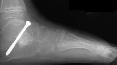

Post operatively, the patient was placed in a long leg cast. Preliminary

results show satisfactory reduction of the talonavicular joint, correction

of hindfoot valgus, dorsiflexion of the talus on the calcaneus, and correction

of forefoot adduction immediately post op.